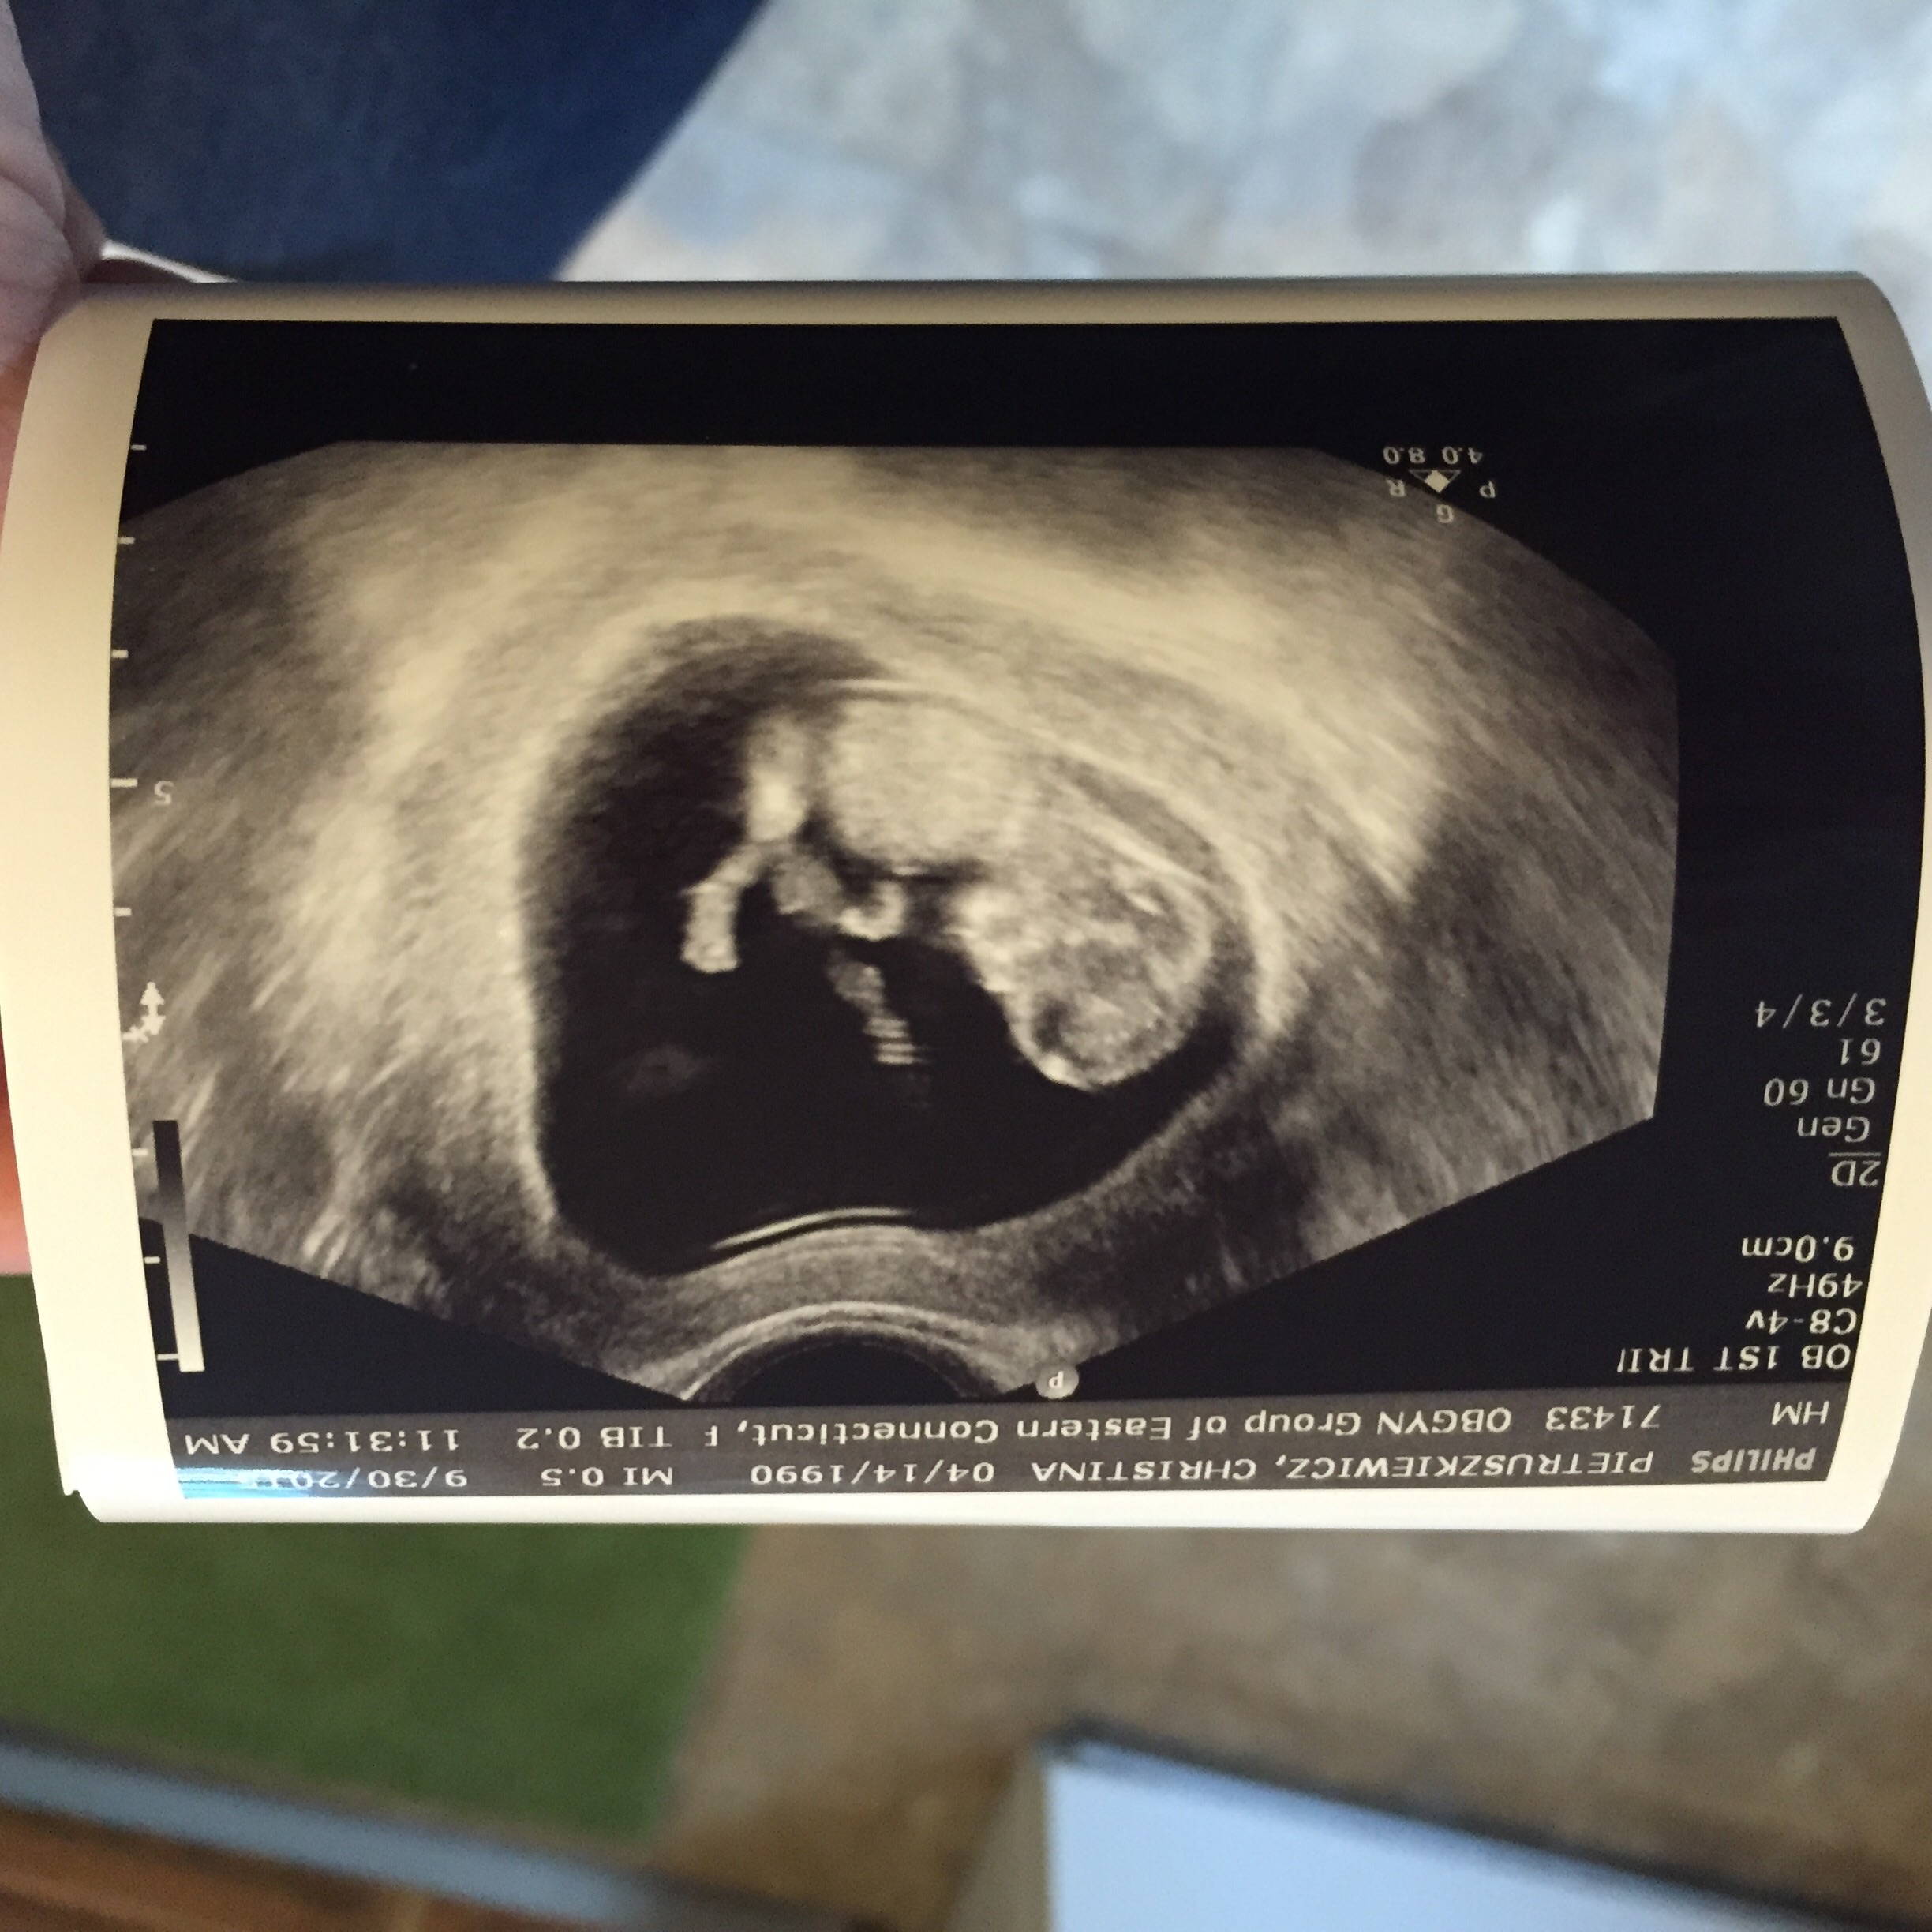

Three weeks ago, baby was measuring a day behind... I'm 11 weeks along today, but baby is now measuring 12 weeks. It was so amazing to watch the little one moving around, waving its arms, and we even got a picture when it was playing with its feet!

We had our second ultrasound last week when I was 11+3. Still measuring a bit bigger, she said I looked about 12 weeks during the scan. Everything looks healthy! Look at that little nose and lips!!!! So in love.